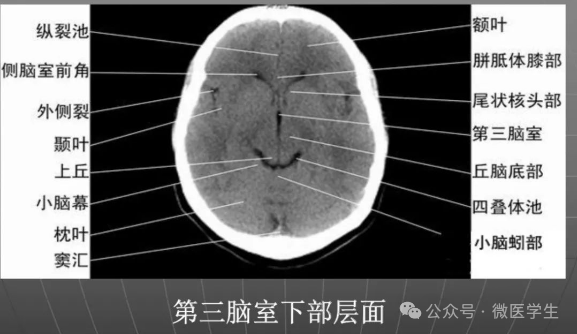

- 颅后窝:四脑室或四叠体池。

显示侧脑室前角的下部:

- 前方—额叶;外侧—尾状核头部;后方中线处—第三脑室,其两侧连接丘脑。

颅后窝:

- “Y”字形或“V”字形的小脑幕,幕下结构在内侧(小脑上蚓部),幕上结构在外侧(枕叶)。

四叠体池:

- 位于小脑蚓部前方。

- 基底核、丘脑。

- 内囊前脚(前肢);尾状核和豆状核之间。

- 内囊膝部和后脚(后肢):位于豆状核(由外侧的壳核和内侧的苍白球组成)及丘脑之间。

- 壳核的外侧:外囊、屏状核、最外囊、岛叶(脑岛)。

- 四叠体池:两侧枕叶之间,池内有松果体,向前与第三脑室连接。